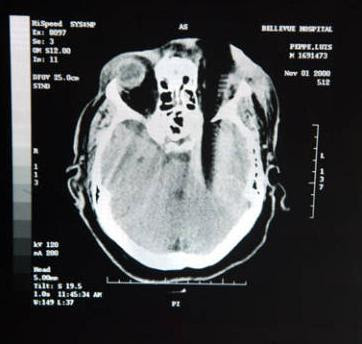

12. Sisir adalah pembunuh.

X-ray Louis Pepe, ketika dia ditikam oleh sisir dalam tengkorak, pada tahun 2000. Ia kehilangan mata kiri dan mata kanannya yang terkena juga. Sisir menyebabkan dia banyak kerusakan: melumpuhkan lengan kanan dan kaki dan kemampuannya untuk berbicara. Penyerang dijatuhi hukuman 23 tahun penjara, gak adil ya gan?